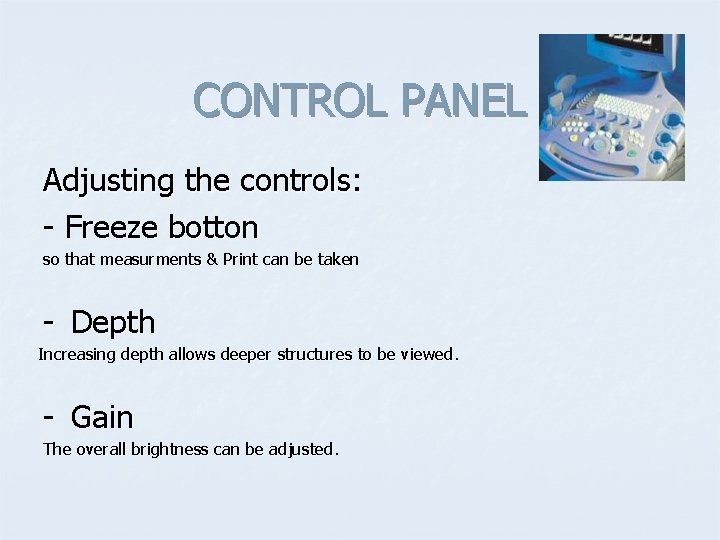

CONTROL PANEL Adjusting the controls: - Freeze botton so that measurments & Print can be taken - Depth Increasing depth allows deeper structures to be viewed. - Gain The overall brightness can be adjusted.